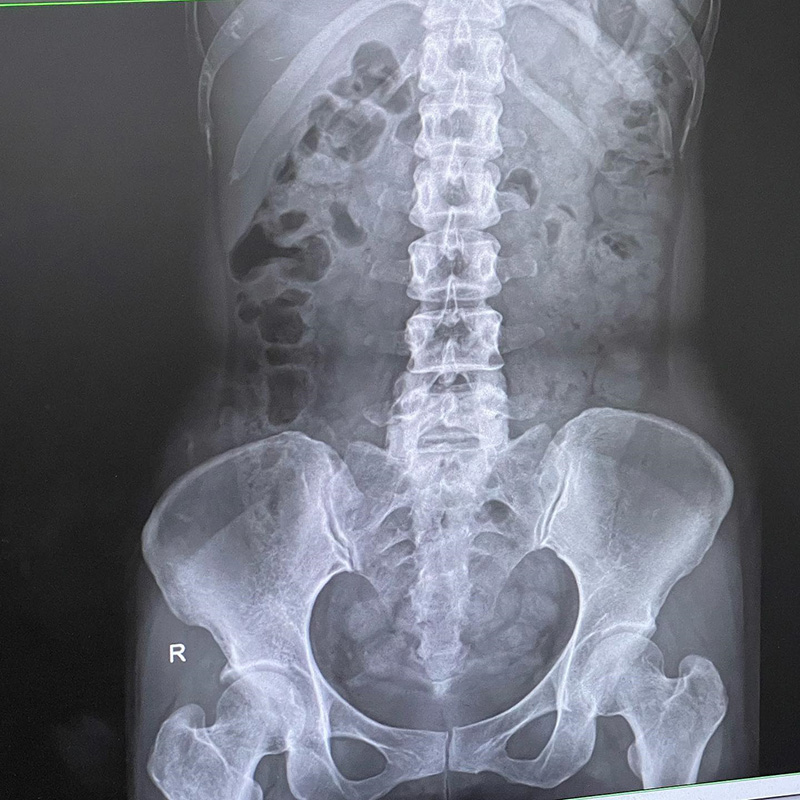

"เลื่อนขวา เพื่อดูฟิล์มเอกซเรย์ หลังจากที่หาหมอจนเจอว่าเป็นโรค (ขอเรียกว่าโรคละกัน) "ขี้เต็มท้อง" พอซัดยาหมอตามอาการเข้าไป วันรุ่งขึ้นเท่านั้น ที่ล็อตแรกได้ถูกปลดปล่อย >> ดีขึ้นทันตาเห็น >> ใช่ละ กรูเป็นหละ สาเหตุนี้

ในฟิล์ม ที่เห็นขาว ๆ ก็คือ ขี้น้อนทั้งนั้นเลยค่ะ ลอยละล่องเป็นยองใย เยอะแค่ไหนถามใจเธอดู"